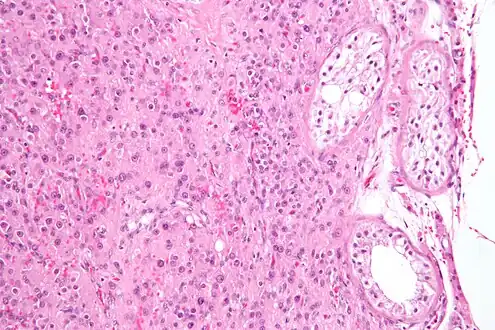

![]() Micrograph showing a cluster of Leydig cells (center of image). H&E stain. | |

Leydig cells, also known as interstitial cells of the testes and interstitial cells of Leydig, are found adjacent to the seminiferous tubules in the testicle and produce testosterone in the presence of luteinizing hormone (LH).[1][2] They are polyhedral in shape and have a large, prominent nucleus, an eosinophilic cytoplasm, and numerous lipid-filled vesicles.[3]

Leydig cells may grow uncontrollably and form a Leydig cell tumour. These may be hormonally active, i.e. secrete testosterone. The function of Reinke crystals is unknown, but they appear in the case of Leydig cell tumours.[5] They are found in less than half of all Leydig cell tumors, but when present, they may serve to confirm the diagnosis of a Leydig cell tumor.[10][11] No other interstitial cell within the testes has a nucleus or cytoplasm with these characteristics, making identification relatively easy.

While any age is susceptible to a Leydig cell tumour, Leydig cell tumours are more common in people aged 5 to 10 and 30 to 35.[12] A Leydig cell tumour in a child usually causes precocious puberty.[12] About 10% of boys with the tumour have gynecomastia.[12] Although a Leydig cell tumour is always benign in children, it is malignant in 10% to 15% of adults.[12] It is the most common testicular cancer of non-germ cell origin.[13]

Intermediate magnification micrograph of a Leydig cell tumour, H&E stain

High magnification micrograph of a Leydig cell tumour, H&E stain